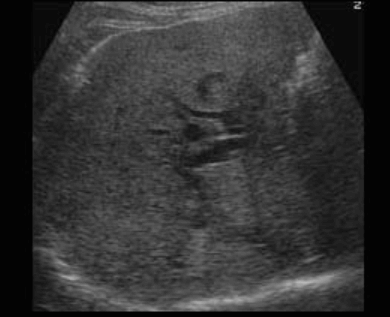

US finding

- 담낭관 또는 담낭 경부에 결석이 확인된다.

- 총간관(CHD) 또는 담낭관(cystic duct)의 확장소견이 보인다.

- 간내외 담관의 확장이 관찰된다.